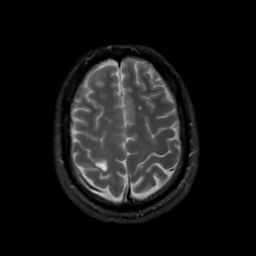

MR Study #13, May 19, 1991 -- Slice #40